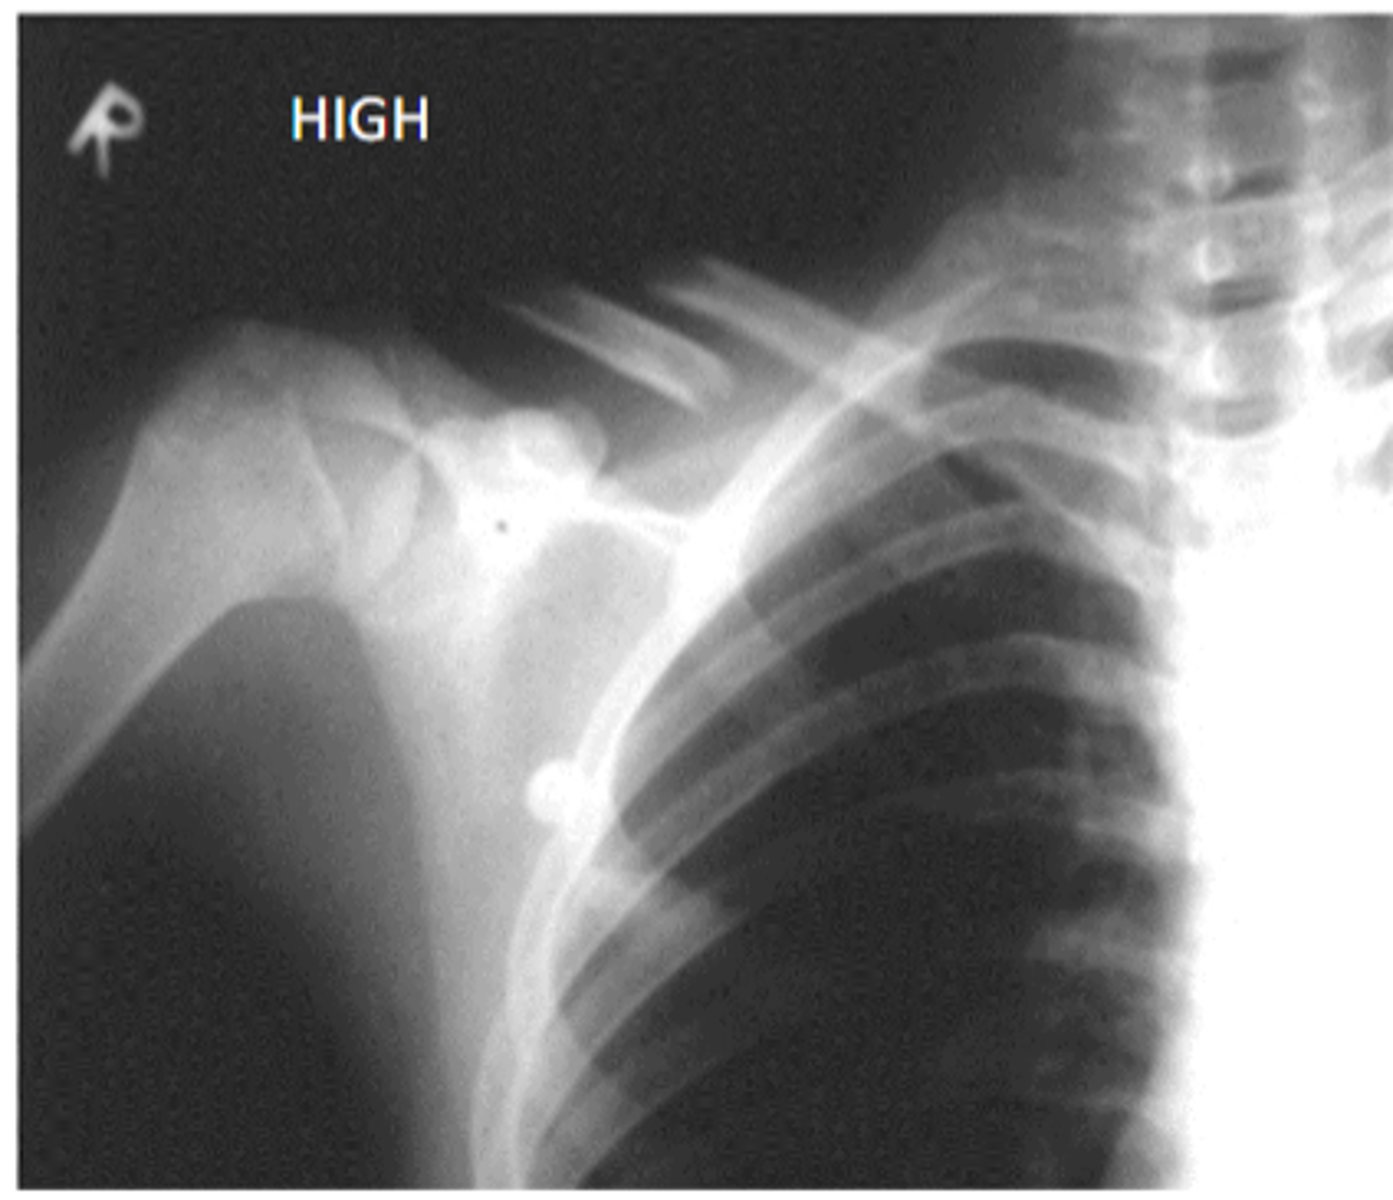

would this image be white or dark

low current with low exposure and close to the beam

white but not as white if the beam was far away